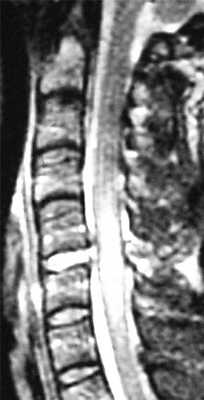

МРТ шейного отдела позвоночника. Острая травма. Компрессия спинного мозга, отек и контузия. Сагиттальная Т2-взвешенная МРТ.

МРТ шейного отдела позвоночника. Т2-взвешенная сагитальная МРТ. Острая травма с повреждением задних элементов позвонков и отеком спинного мозга.

МРТ шейного отдела позвоночника. Острая травма. Отёк спинного мозга. Сагиттальная Т2-взвешенная МРТ.